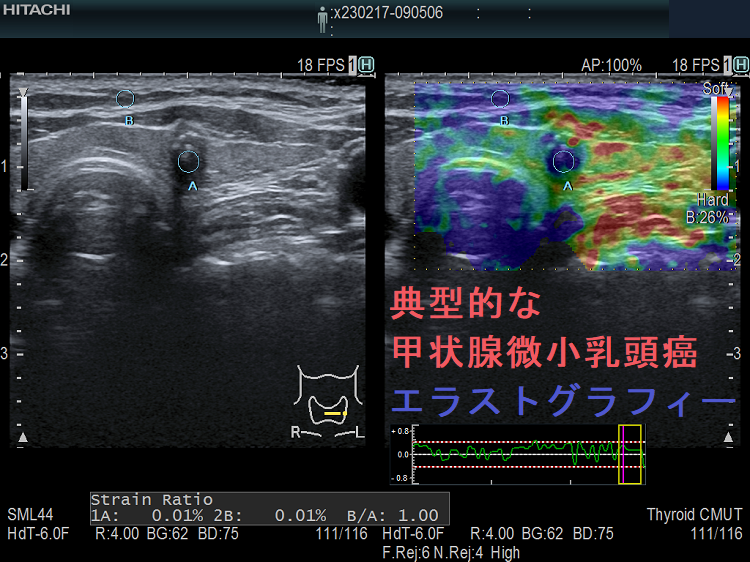

典型的な甲状腺微小乳頭癌 エラストグラフィー

甲状腺微小乳頭癌も典型的にはエラストグラフィーで硬く(青く)見えます。

エラストグラフィーを用いた甲状腺微小癌の

1. 感度88.9%

2. 特異度89.3%

3. 誤診率10.7%

4. 見逃し率11.1%

5. 診断適合率89.2%

です。約90%は診断可能ですが、診断不能な甲状腺微小癌は約10%存在します。[Pak J Med Sci. 2019 Nov-Dec;35(6):1526-1531.]